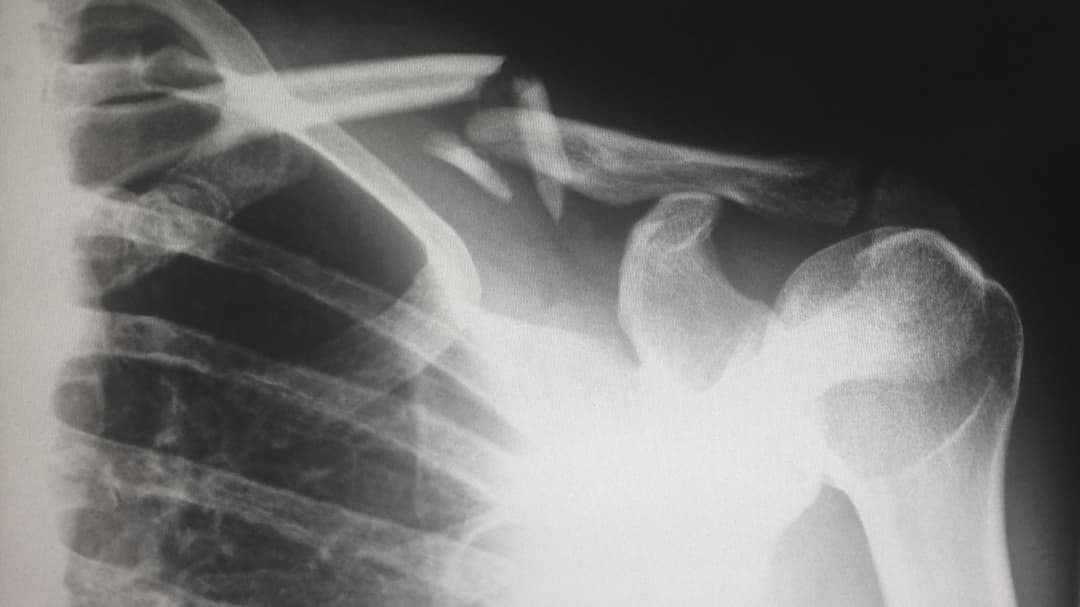

レントゲン写真